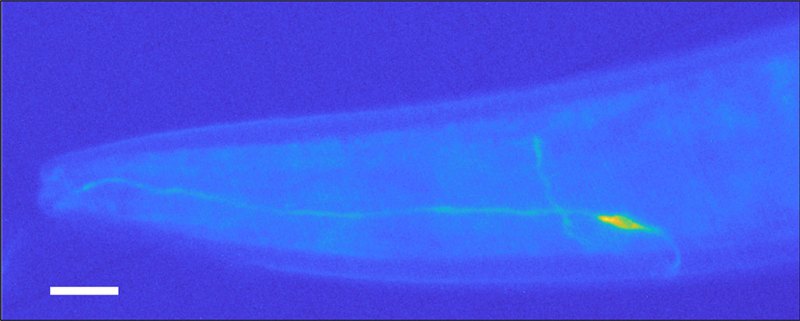

This microscopic image shows Caenorhabditis elegans nematodes, small worms being used in a new system to sniff out cancer.

The worms’ simplicity has even allowed scientists to pinpoint the exact nerve cell that reacts to cancer cell aromas. Enrico Lanza, a physicist who studies neuroscience with Folli, did this by genetically tweaking some of the wigglers so that when a specific neuron got activated, it lit up. He then exposed the worms to diseased cells and examined them under a microscope, looking for glow-in-the-dark cells.

“C. elegans is transparent,” Lanza says. “So if something lights up inside [it]…you can detect it from the outside.” And something did light up — a single, radiant neuron located at one end of C. elegans. Lanza snapped a picture.